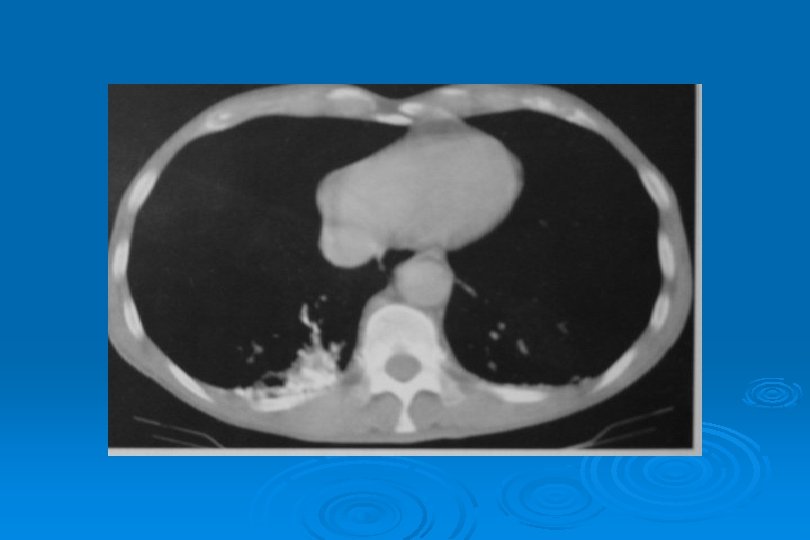

SİTOMEGALOVİRÜS • Birden fazla odakda, iki taraflı buzlu cam yoğunluğu ve konsolidasyon alanları • Milimetrik nodüller